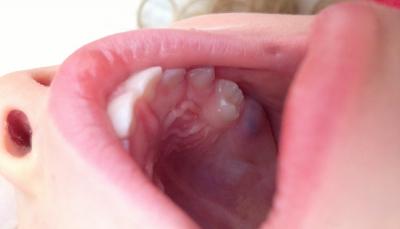

- Ретинированный зуб. Прорезывается частично или полностью остаётся в кости, не выходя наружу. Даже если пациента с ретинированной восьмёркой ничего не беспокоит, велик риск возникновения всевозможных инфекций в будущем, постоянного воспаления десны, появления кариеса, пародонтоза и т.д.

- Воспаление. Развивающийся перикоронарит – патология, возникающая при затруднённом прорезывании моляра, несёт риск инфицирования околозубной ткани и капюшона десны, прикрывающей растущий моляр, вероятен также отёк и нагноение дёсенной ткани.